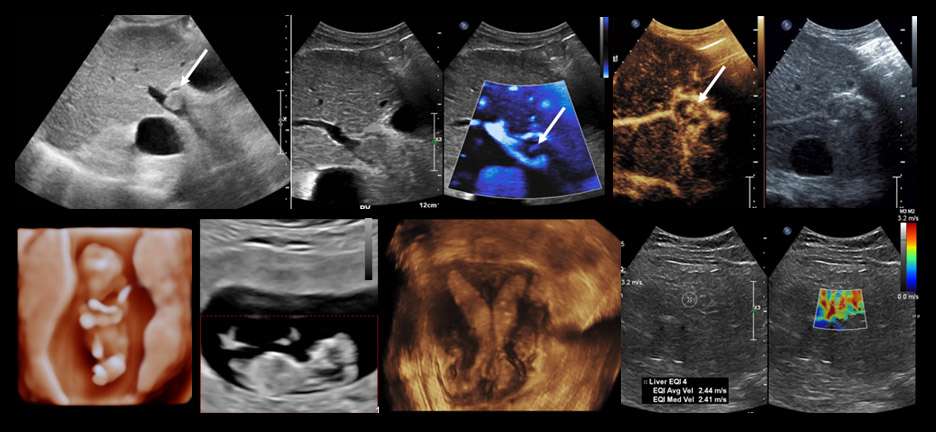

UCLA Health Ultrasonography serves the Los Angeles area with the full array of ultrasound procedures, including general abdominal, gynecologic-obstetric-fetal, urologic, head-neck-thyroid and vascular examinations. Our specialists use the most advanced techniques, including color-flow Doppler and superb microvascular imaging, 3-D ultrasound, shear-wave elastography, and contrast enhanced ultrasound.

Ultrasound directed procedures including biopsies, aspirations and saline infusion sonohysterograms are performed in our outpatient centers. All ultrasound facilities are equipped with high resolution 2-D grayscale and color-flow Doppler scanning equipment applying the latest software platform where available. Our specialists also conduct ongoing research in many projects including application of artificial intelligence technologies in image analysis.